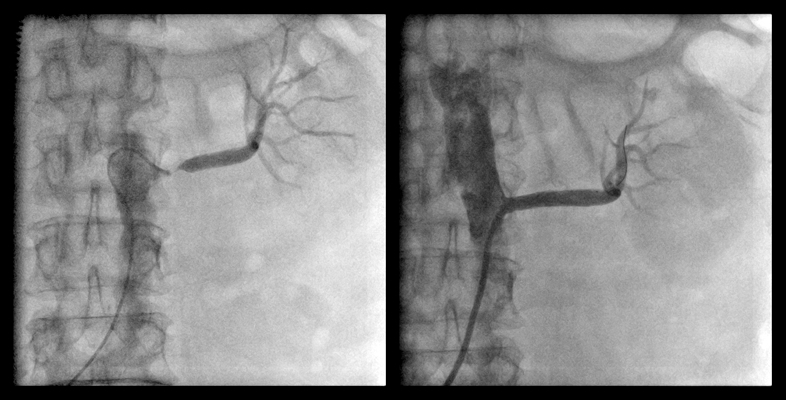

ガイドワイヤー通過

バルーン拡張

ステント留置

血管内手術

- 浅大腿動脈狭窄 【写真】

- 浅大腿動脈閉塞 【写真】

考え方としては、早期であるほど2の血管内手術のみで治る可能性が高いと考えてよいでしょう。現在の末梢動脈に対する血管内手術の適応は、大動脈・腸骨動脈領域から膝下動脈、さらに足関節から足趾にまで及びます。しかし、それぞれの治療法には当然ながら適応があります。このためしばしば従来からの手術との組み合わせであるハイブリッド手術が必要になりますが、血管内呪術の関与する割合は8~9割にも及んでいます。